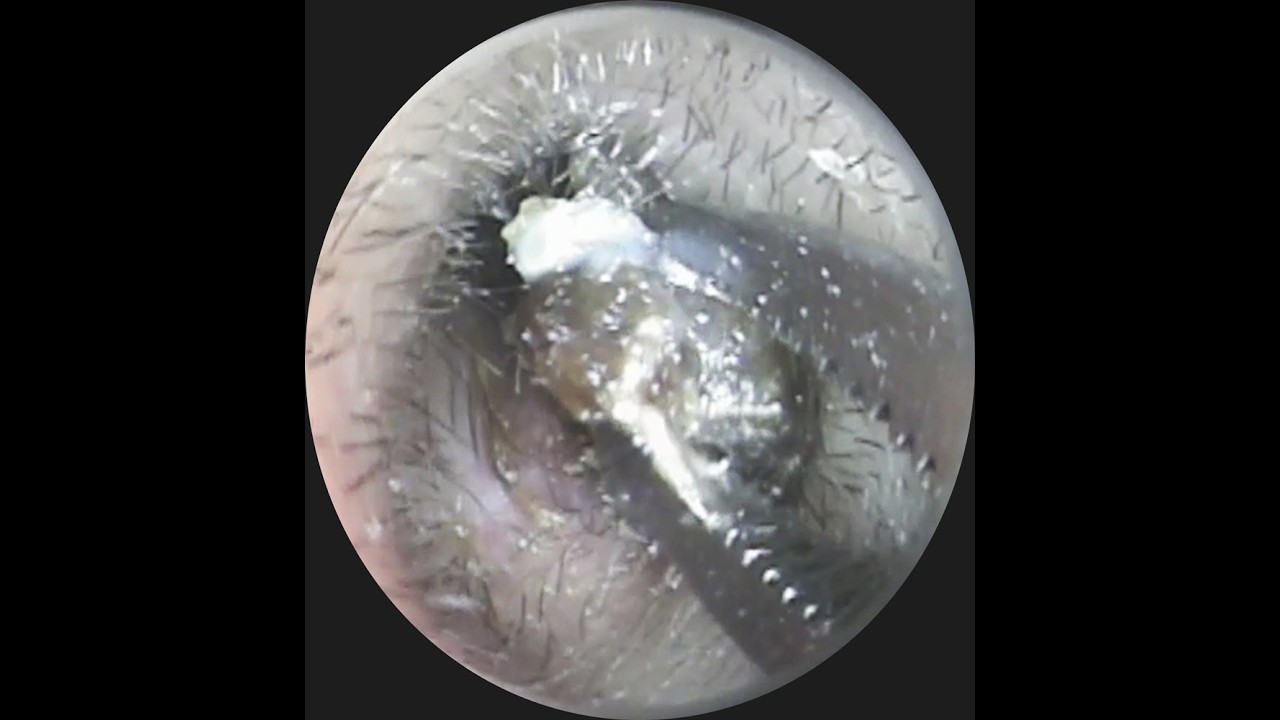

「あなたは大丈夫?」自分で押し込んだ耳垢とイヤホンで押し込まれた耳垢が・・・ #イヤーエステ #耳掃除 #eariss #イヤーエステ #耳掃除 サロン#耳かき動画

公開日:2026/05/21